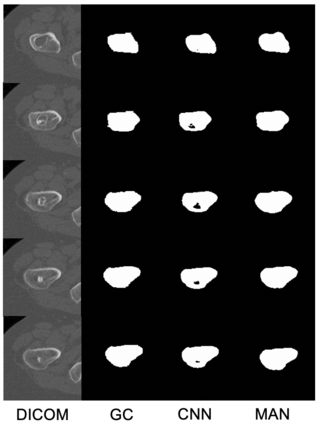

Osteoporosis is a common bone disease that increases the risk of bone fracture. Hip-fracture risk screening methods based on finite element analysis depend on segmented computed tomography (CT) images; however, current femur segmentation methods require manual delineations of large data sets. Here we propose a deep neural network for fully automated, accurate, and fast segmentation of the proximal femur from CT. Evaluation on a set of 1147 proximal femurs with ground truth segmentations demonstrates that our method is apt for hip-fracture risk screening, bringing us one step closer to a clinically viable option for screening at-risk patients for hip-fracture susceptibility.